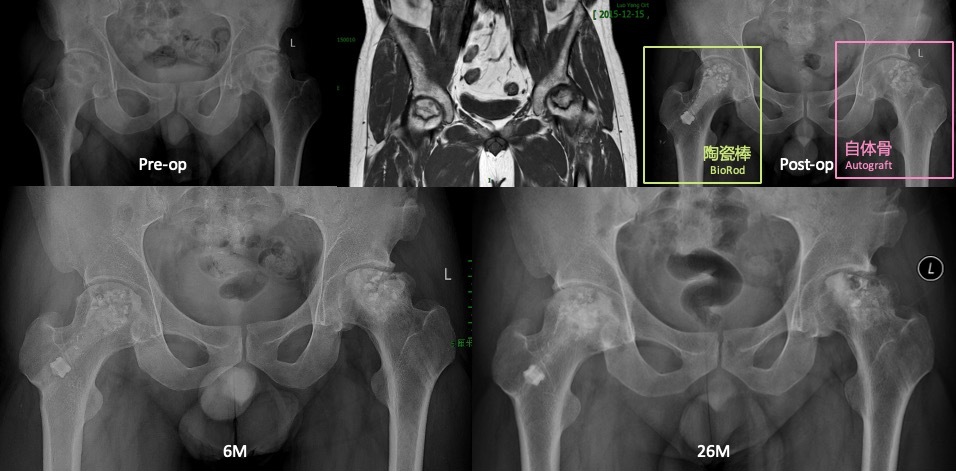

陶瓷棒架桥引血技术治疗股骨头坏死”获得国家药监局批发的三类医疗器械注册证后已在全国数百家医院治疗患者近万例。2019发表于《中国修复重建外科杂志》的200例股骨头坏死治疗的跟踪研究,发现临床有效率达到93.1%(II期96%,III期87.8%),关节功能评分提升38%,优良率达64.22%的国际先进水平。2018发表于《International Orthopaedics》的72髋股骨头坏死陶瓷棒治疗的跟踪研究,平均随访 26.7月,临床有效率超过90%(II期92.9%,III期86.7%),高于现有的保髋技术。据数30篇文献报道统计,手术成功率超过90%,HSS平均改善36%。 |